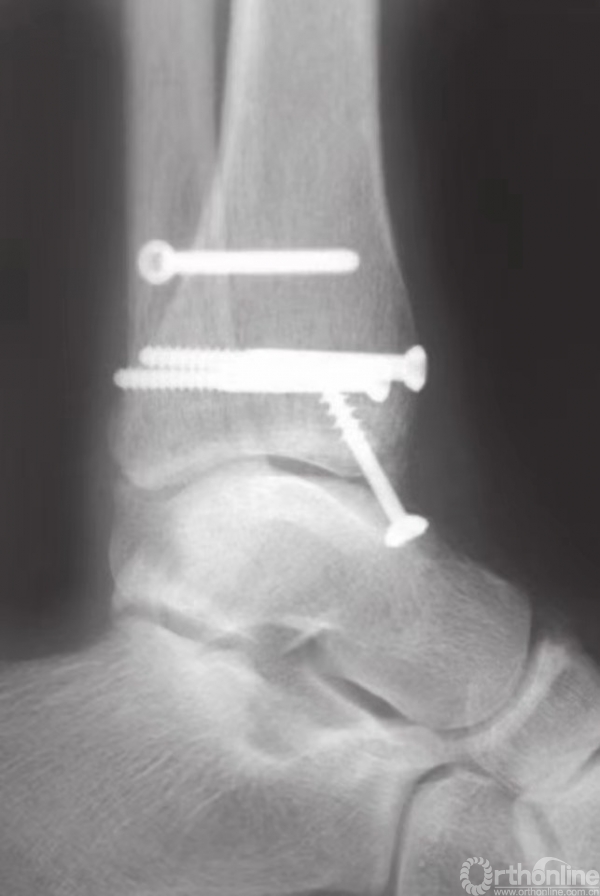

在钳的前方和后方,放置两枚较小的克氏针,并使之与骨折线垂直(图15)。注意要保证克氏针不刺穿踝关节(图16)。为防止刺穿关节,可将角度调至与水平方向约成30°。在克氏针上方和对侧皮质附近,使用管状钻钻孔。后嵌入4mm部分有螺纹的空心松质骨螺钉。

在骨折片尖部固定螺钉时,三角韧带表层可能会部分劈裂。再将另一枚螺钉以相同方式嵌入(图17),无需涉及对侧皮质。在大多数病例中,40或45mm长度规格的螺钉可以起到很好的固定作用。这些螺钉应相互平行,并在内踝骨折片上方铺开,以便更好地控制旋转(图18)。

图17 半螺纹松质骨空心钉最终固定骨折

图18 内踝固定完成

通过X线透视确认骨折复位和螺钉的固定(图19)。用可吸收缝线缝合较薄的皮下层后,再将皮肤缝合。

图19 通过X线透视确认骨折复位和螺钉的固定